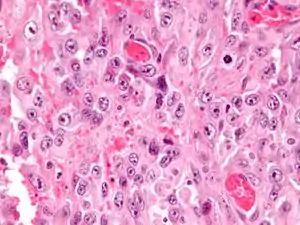

| Micrograph of an epithelioid sarcoma. H&E stain. | |

Histologically, epithelioid sarcoma forms nodules with central necrosis surrounded by bland, polygonal cells with eosinophilic cytoplasm and peripheral spindling.[3] Epithelioid sarcomas typically express vimentin, cytokeratins, epithelial membrane antigen, and CD34, whereas they are usually negative for S100, desmin, and FLI1 (FLI-1).[3] They typically stain positive for CA125.[4]